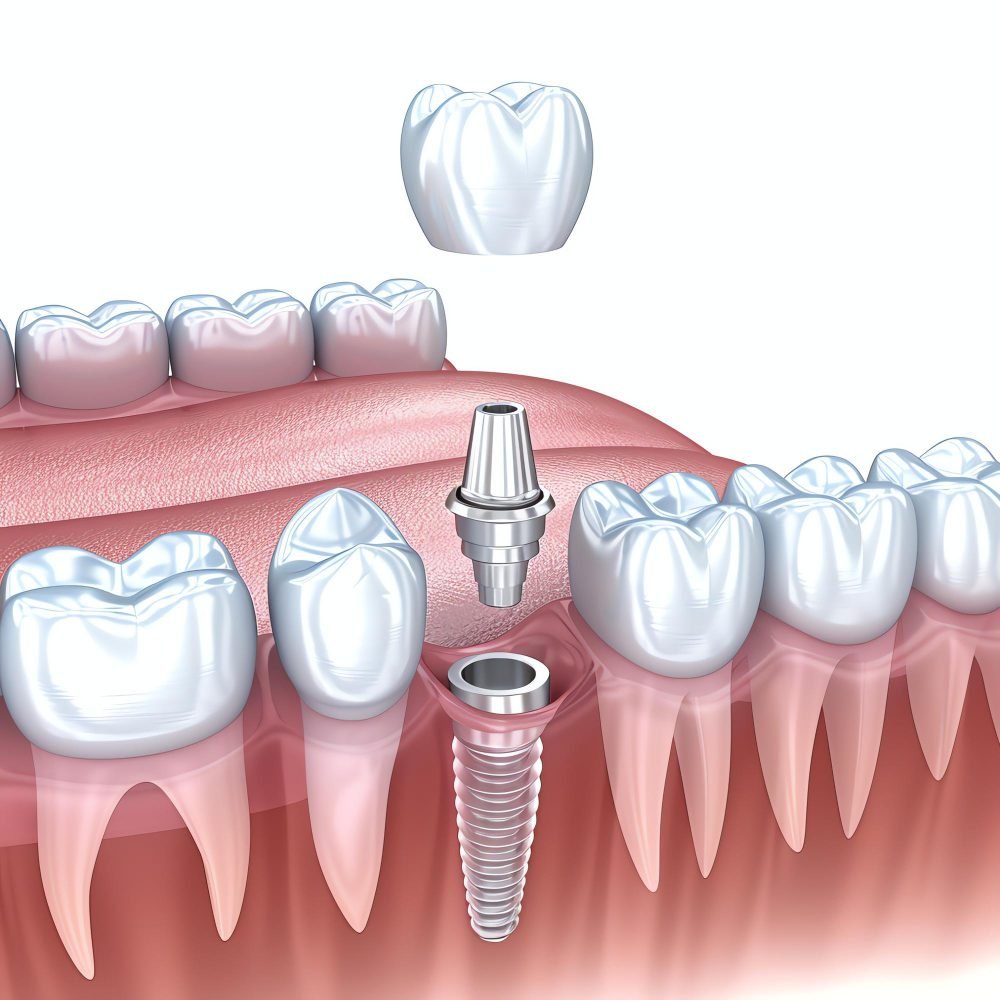

زراعة الأسنان (Dental Implant) هي عبارة عن جذر صناعي من التيتانيوم يوضع في عظم الفك لتعويض سن مفقود، ثم تُركب عليه تاج أو جسر يهدف لاستعادة الشكل والوظيفة الطبيعية للأسنان.

- تركيب الدعامة (Abutment)

- توصيل الدعامة بالزرعة

- تركيب التثبيت النهائي (Crown/Bridge)